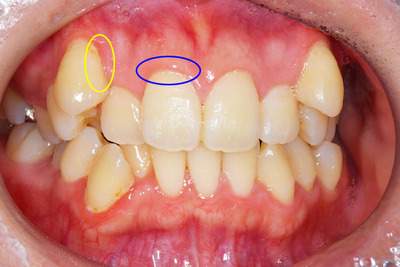

AFTER

歯周病症例の治療後

黄色:歯の周りに付着していた黒い歯石がなくなっています。

青色:歯石を除去することでは周囲の歯ぐきの色がピンク色になっているのがわかります。これは炎症がおさまったことを意味します。

年齢・性別 30代・女性

主訴 歯のクリーニングをしたい

治療内容 歯石除去(スケーリング、再評価)

治療費 約2,000円(保険治療内)

治療期間 2週間(歯石を除去して、歯肉の回復を待つのに2週間待機します)

リスク・副作用 歯石除去後は歯ぐきがひきしまるため、歯が伸びたような感じになることがあります。

また、歯が冷たいものにしみやすくなることもあります。